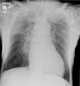

Chronic Kerley lines

Kerley lines are a sign seen on chest radiographs with interstitial pulmonary edema. They are thin linear pulmonary opacities caused by fluid or cellular infiltration into the interstitium of the lungs. [Source: Wikipedia ]